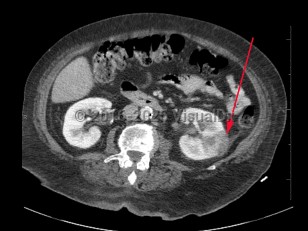

Hydronephrosis

Renal calculus

Polycystic kidney diseasePolycystic kidney disease

Pyelonephritis